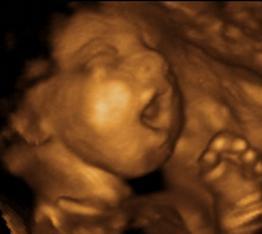

First scan (The 11-13 weeks scan) This scan is carried out from 11 weeks to 13 weeks and six days. The scan is usually performed transabdominally but in a few cases it may be necessary to do the examination transvaginally.

fetal yawning